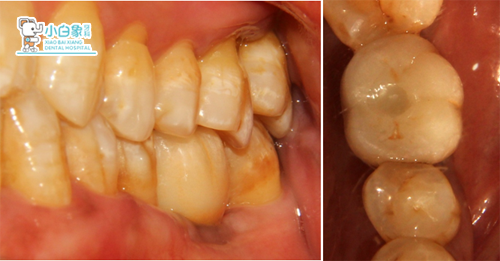

36戴牙

一周后复查